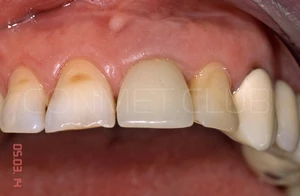

Фото этой же коронки через 15 лет после операции.

Вид на палатинальную поверхность.

15 лет полноценной функциональной нагрузки.